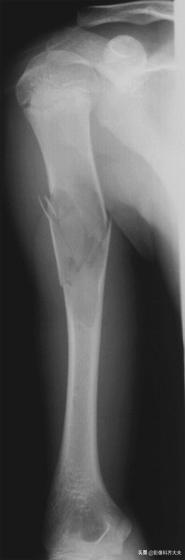

定义:连续、多次轻微损伤如长期负重、跳跃、行走及运动起步过猛等可造成疲劳骨折,跖、趾骨,胫腓骨为好发部位。

X线表现:骨折线横行、光滑,常发生于皮质一侧;骨折线周边可出现骨膜增生及骨痂形成;骨折线相应骨皮质可增厚,髓腔硬化;短时间内骨痂可逐渐变大,又在短时间内逐渐变小好转。

肱骨骨折